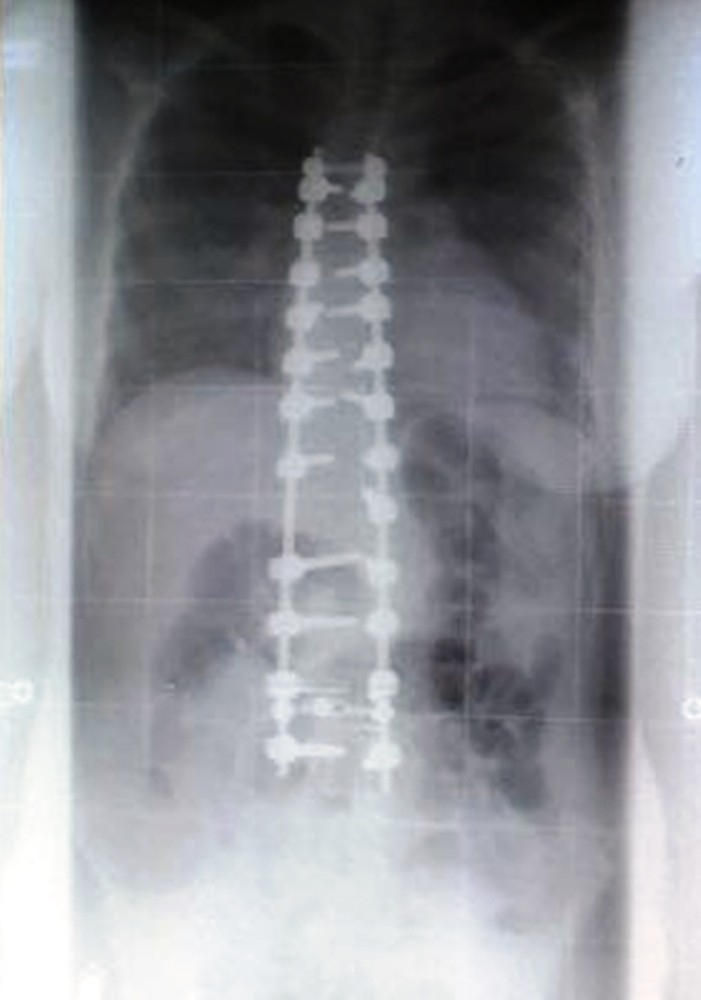

Medikal Park Karadeniz Hastanesinde Ortopedi ve Travmatoloji uzmanı Prof Dr. Çetin Önder, skolyoz cerrahisindeki amacın eğilmiş omurları düzgün bir şekilde dizip birbirine kaynatarak, kaynama sonrasında bu bölge tek bir kemik gibi hareket etmek olduğunu söyledi.

Günümüz teknolojisi skolyoz cerrahlarının eğrilikleri düzeltebilme yeteneklerini artığını söyleyen Önder, "Böylece estetik olarak düzgün bir görüntü elde edilebilir. Eğrilmiş omurların birbirine kaynatıldığı füzyon ameliyatı skolyoz eğriliğinin artmasını engellemekte çok başarılıdır. Omurlar omuriliği korumakla da görevlidirler. Dolayısıyla ameliyat sırasında omuriliğe zarar vermemek için güvenli kalınabilen maksimum düzeltmeyi elde etmeye çalışırlar. Ameliyat kararını deneyimli bir omurga cerrahı ile görüşüldükten sonra ameliyata almak en doğrusudur" diye konuştu.